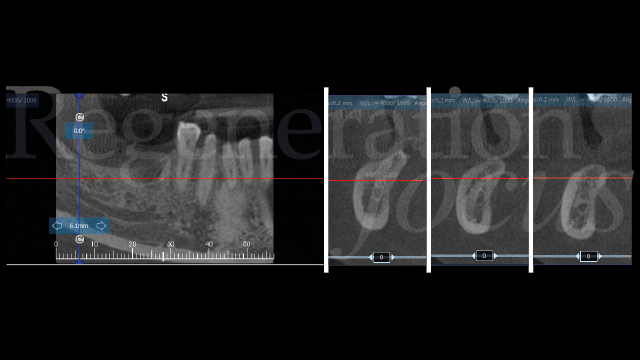

Una paziente di 44 anni, non fumatrice e in buone condizioni di salute generale, si è presentata riferendo significative difficoltà masticatorie, nel quarto quadrante, conseguenti alla perdita del ponte 45-47 per complicanze endodontico-protesiche. L’anamnesi medica non rivelava patologie sistemiche di rilievo né assunzione di farmaci che potessero interferire con i processi di guarigione ossea. L’esame intraorale evidenziava una discreta atrofia della cresta alveolare edentula con collasso vestibolo-linguale dei tessuti molli (Fig. 1). Gli elementi dentari adiacenti presentavano condizioni parodontali stabili. L’analisi radiografica tridimensionale, mediante CBCT, ha permesso una valutazione dettagliata del deficit osseo (Fig. 2). Dopo discussione delle diverse opzioni terapeutiche, inclusa la possibilità di impianti corti, si è optato per una rigenerazione ossea guidata mediante mesh customizzata.